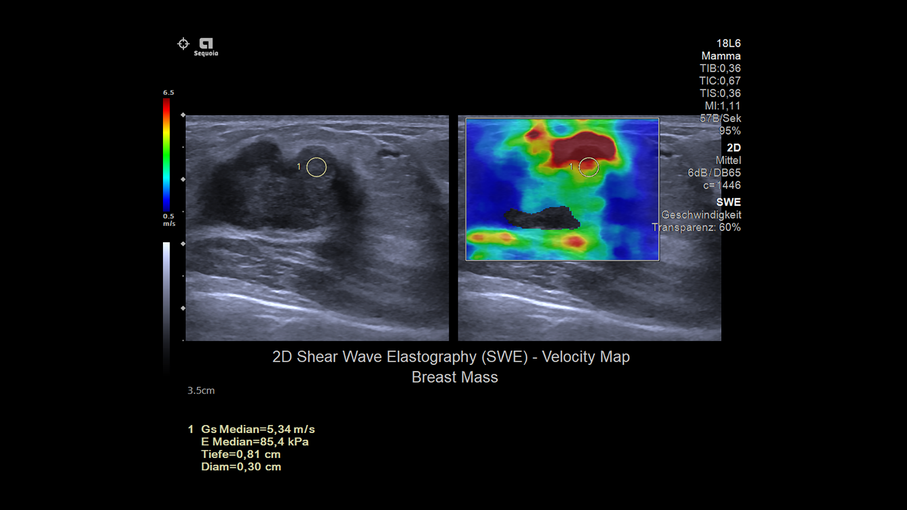

Кроме новой техники, можно заказать восстановленные медицинские системы: ультразвуковые сканеры, томографы, флюороскопы, ангиографы и хирургические установки С-дуга.